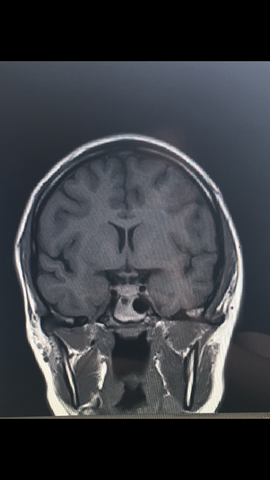

Mrt Gehirn T1 Gewichtet Nativ

Mrt Gehirn T2 Gewichtet Nativ

Gehirn Mrt Atlas Der Menschlichen Anatomie